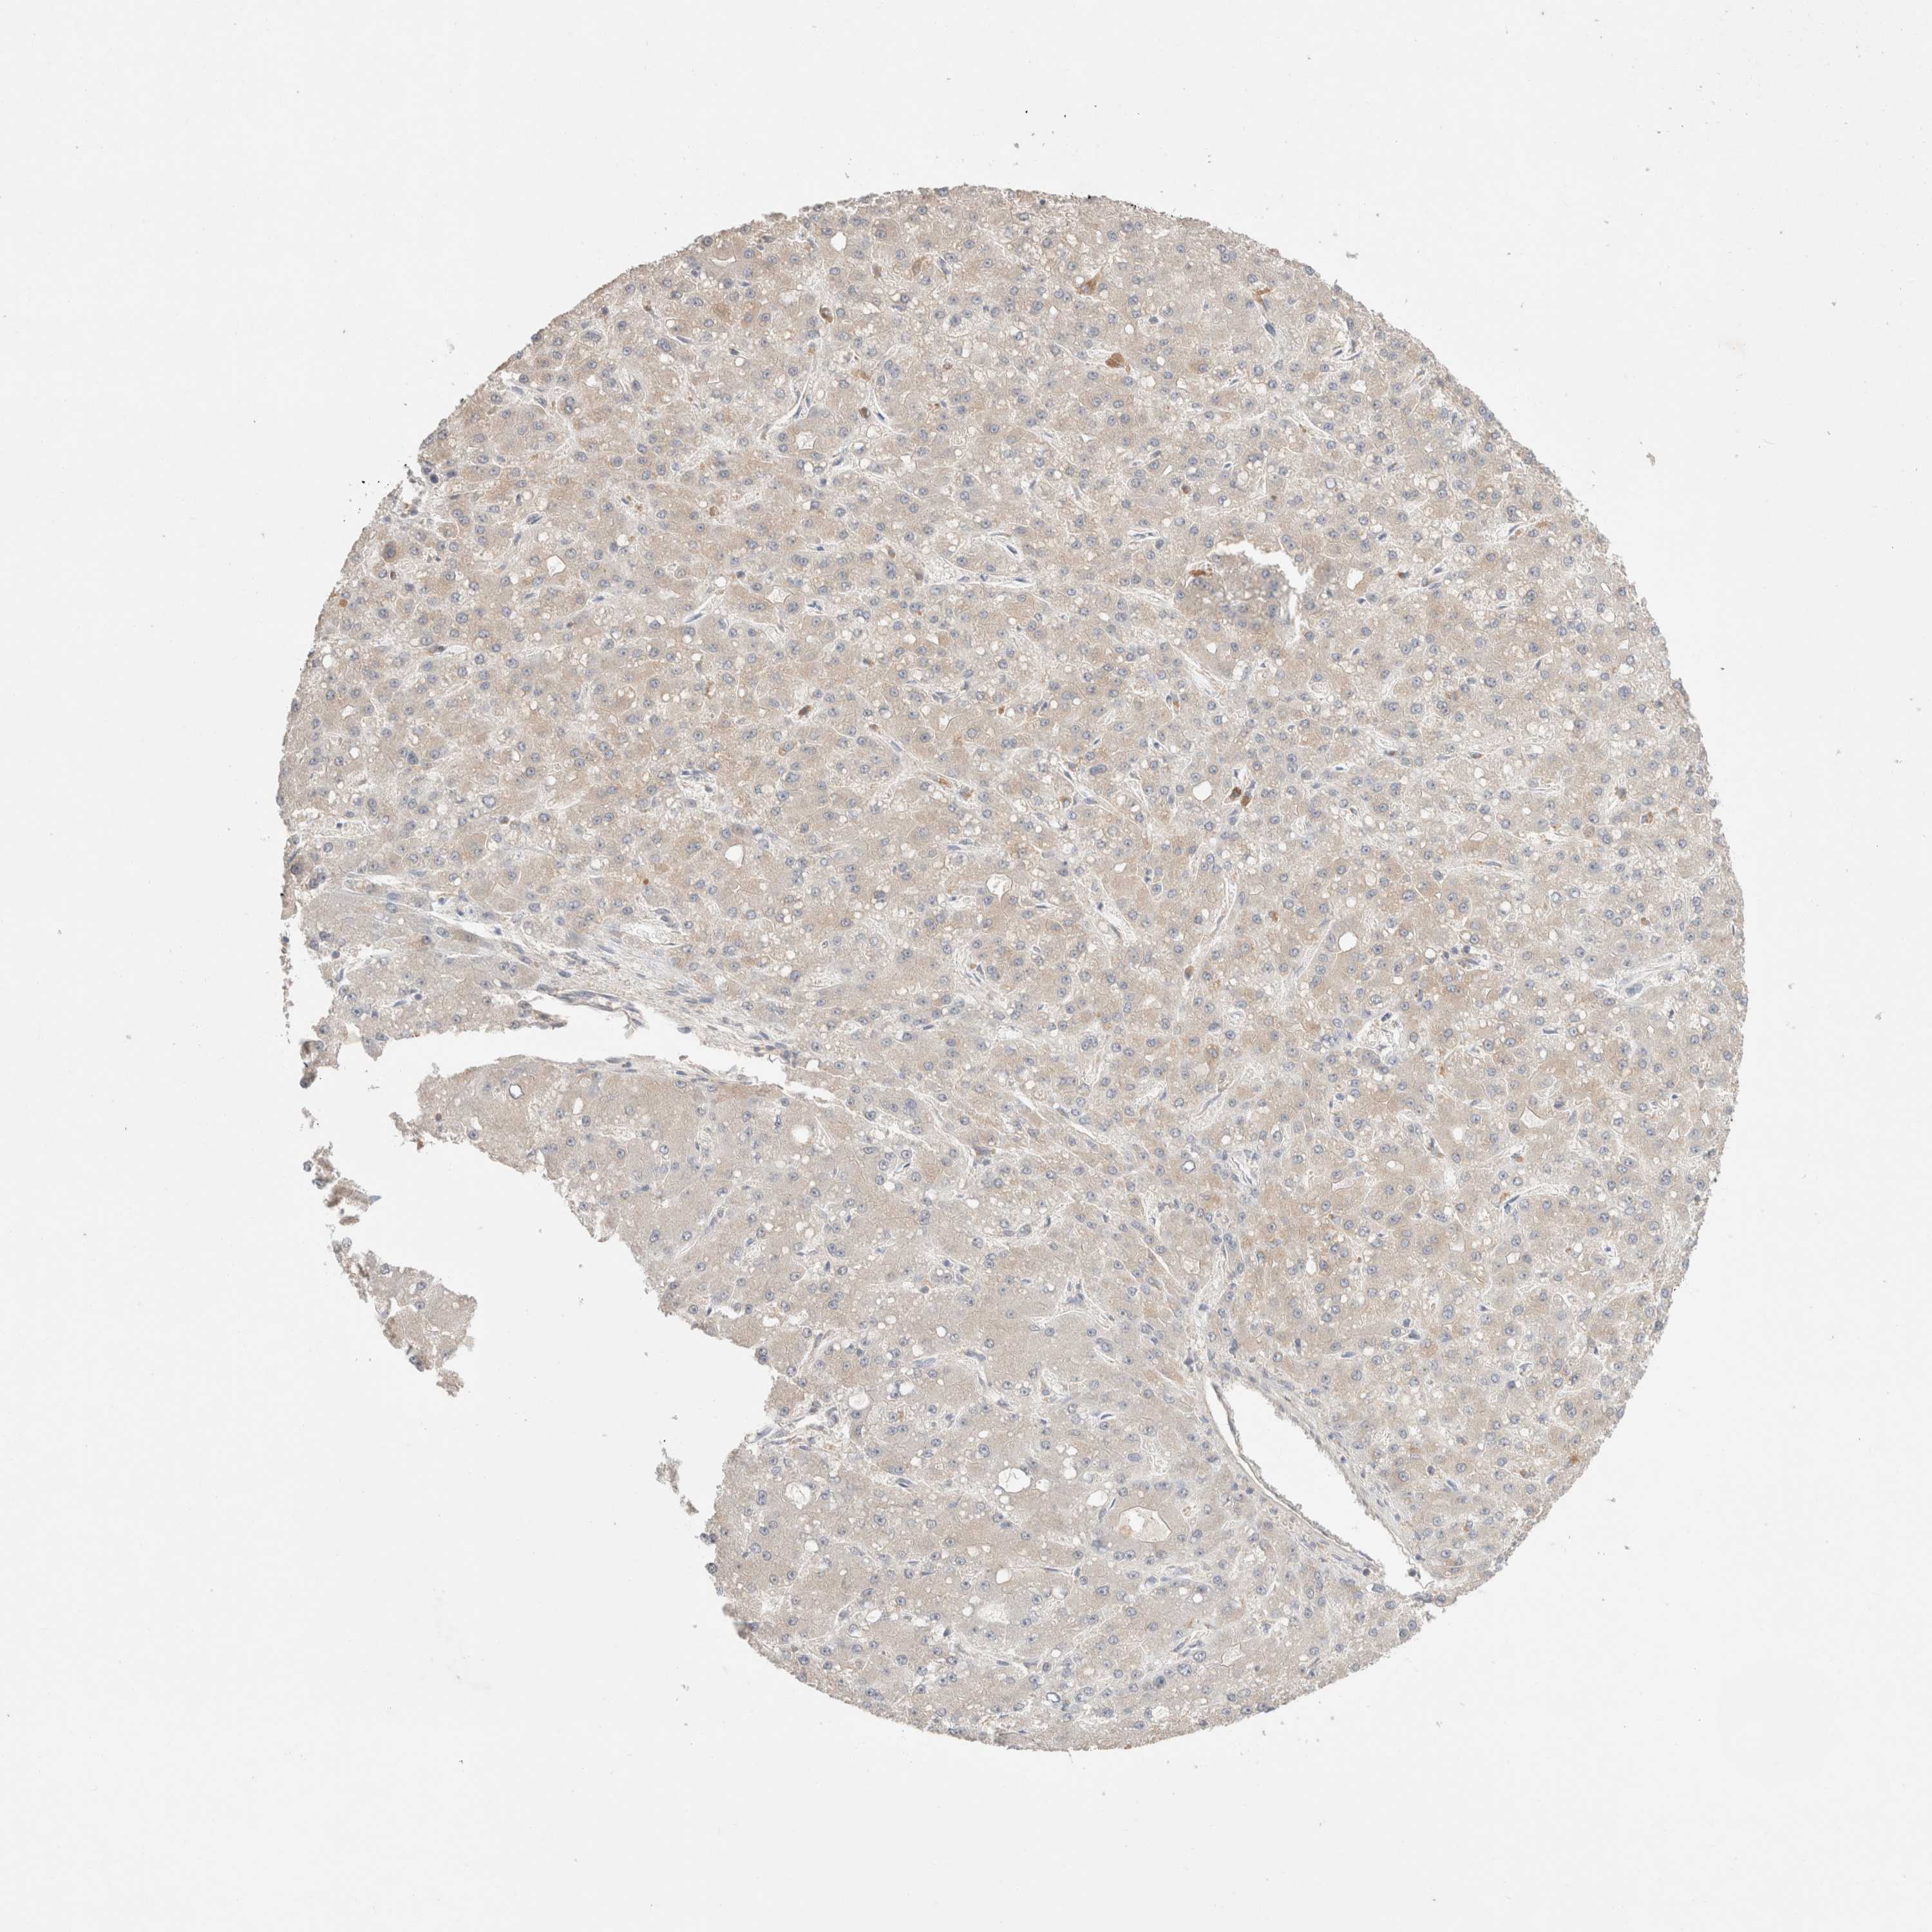

LIVER CANCER - Protein expressioni

A mouse-over function shows sample information and annotation data. Click on an image to view it in a full screen mode. Samples can be filtered based on level of antibody staining by selecting one or several of the following categories: high, medium, low and not detected. The assay and annotation is described here.

Note that samples used for immunohistochemistry by the Human Protein Atlas do not correspond to samples in the TCGA dataset.

Antibody stainingi

Antibody staining in the annotated cell types in the current human tissue is reported as not detected, low, medium, or high, based on conventional immunohistochemistry profiling in selected tissues. This score is based on the combination of the staining intensity and fraction of stained cells.

Each image is clickable and will lead to virtual microscopy that enables deeper exploration of all samples and also displays staining intensity scores, fraction scores and subcellular localization as well as patient and tissue information for each sample.

Antibody HPA024204

Staining

High

Medium

Low

Not detected

Intensity

Strong

Moderate

Weak

Negative

Quantity

>75%

75%-25%

<25%

None

Location

Nuclear

Cytoplasmic/membranous

Cytoplasmic/membranous,nuclear

Cholangiocarcinoma

Carcinoma, Hepatocellular, NOS